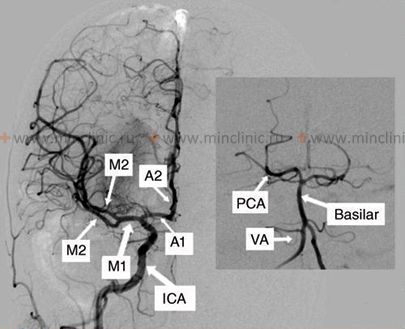

Наиболее надёжным методом исследования сосудистой сети головного мозга служит церебральная ангиография. Процедура ангиографии проводимая путём избирательного введения контрастного вещества после катетеризации бедренной артерии. Селективная ангиография позволяет обнаружить язвенные поражения стенки артерии, выраженное её сужение (стеноз), образование пристеночного тромба в области каротидной бифуркации. Так же селективная ангиография даёт возможность непосредственно увидеть расслоение стенки сонной артерии и поражение её сифона и других сосудов (артерий) головного мозга атеросклерозом с тромбозом. С помощью селективной ангиографии можно обнаружить коллатеральный кровоток в виллизиевом круге и на кортикальной поверхности, эмболическую окклюзию ветвей сосудов мозга.

Хотя с помощью ангиографии невозможно определить кровоток, она фиксирует некоторые изменения, свидетельствующие о его нарушениях в системе внутренней сонной артерии. Например, внутримозговое артериальное русло может заполняться медленнее, чем наружная сонная артерия. Таким образом, церебральная ангиография позволит врачу оценить многие факторы, имеющие отношение к пониманию патологической физиологии природы инсульта (инфаркта головного мозга).